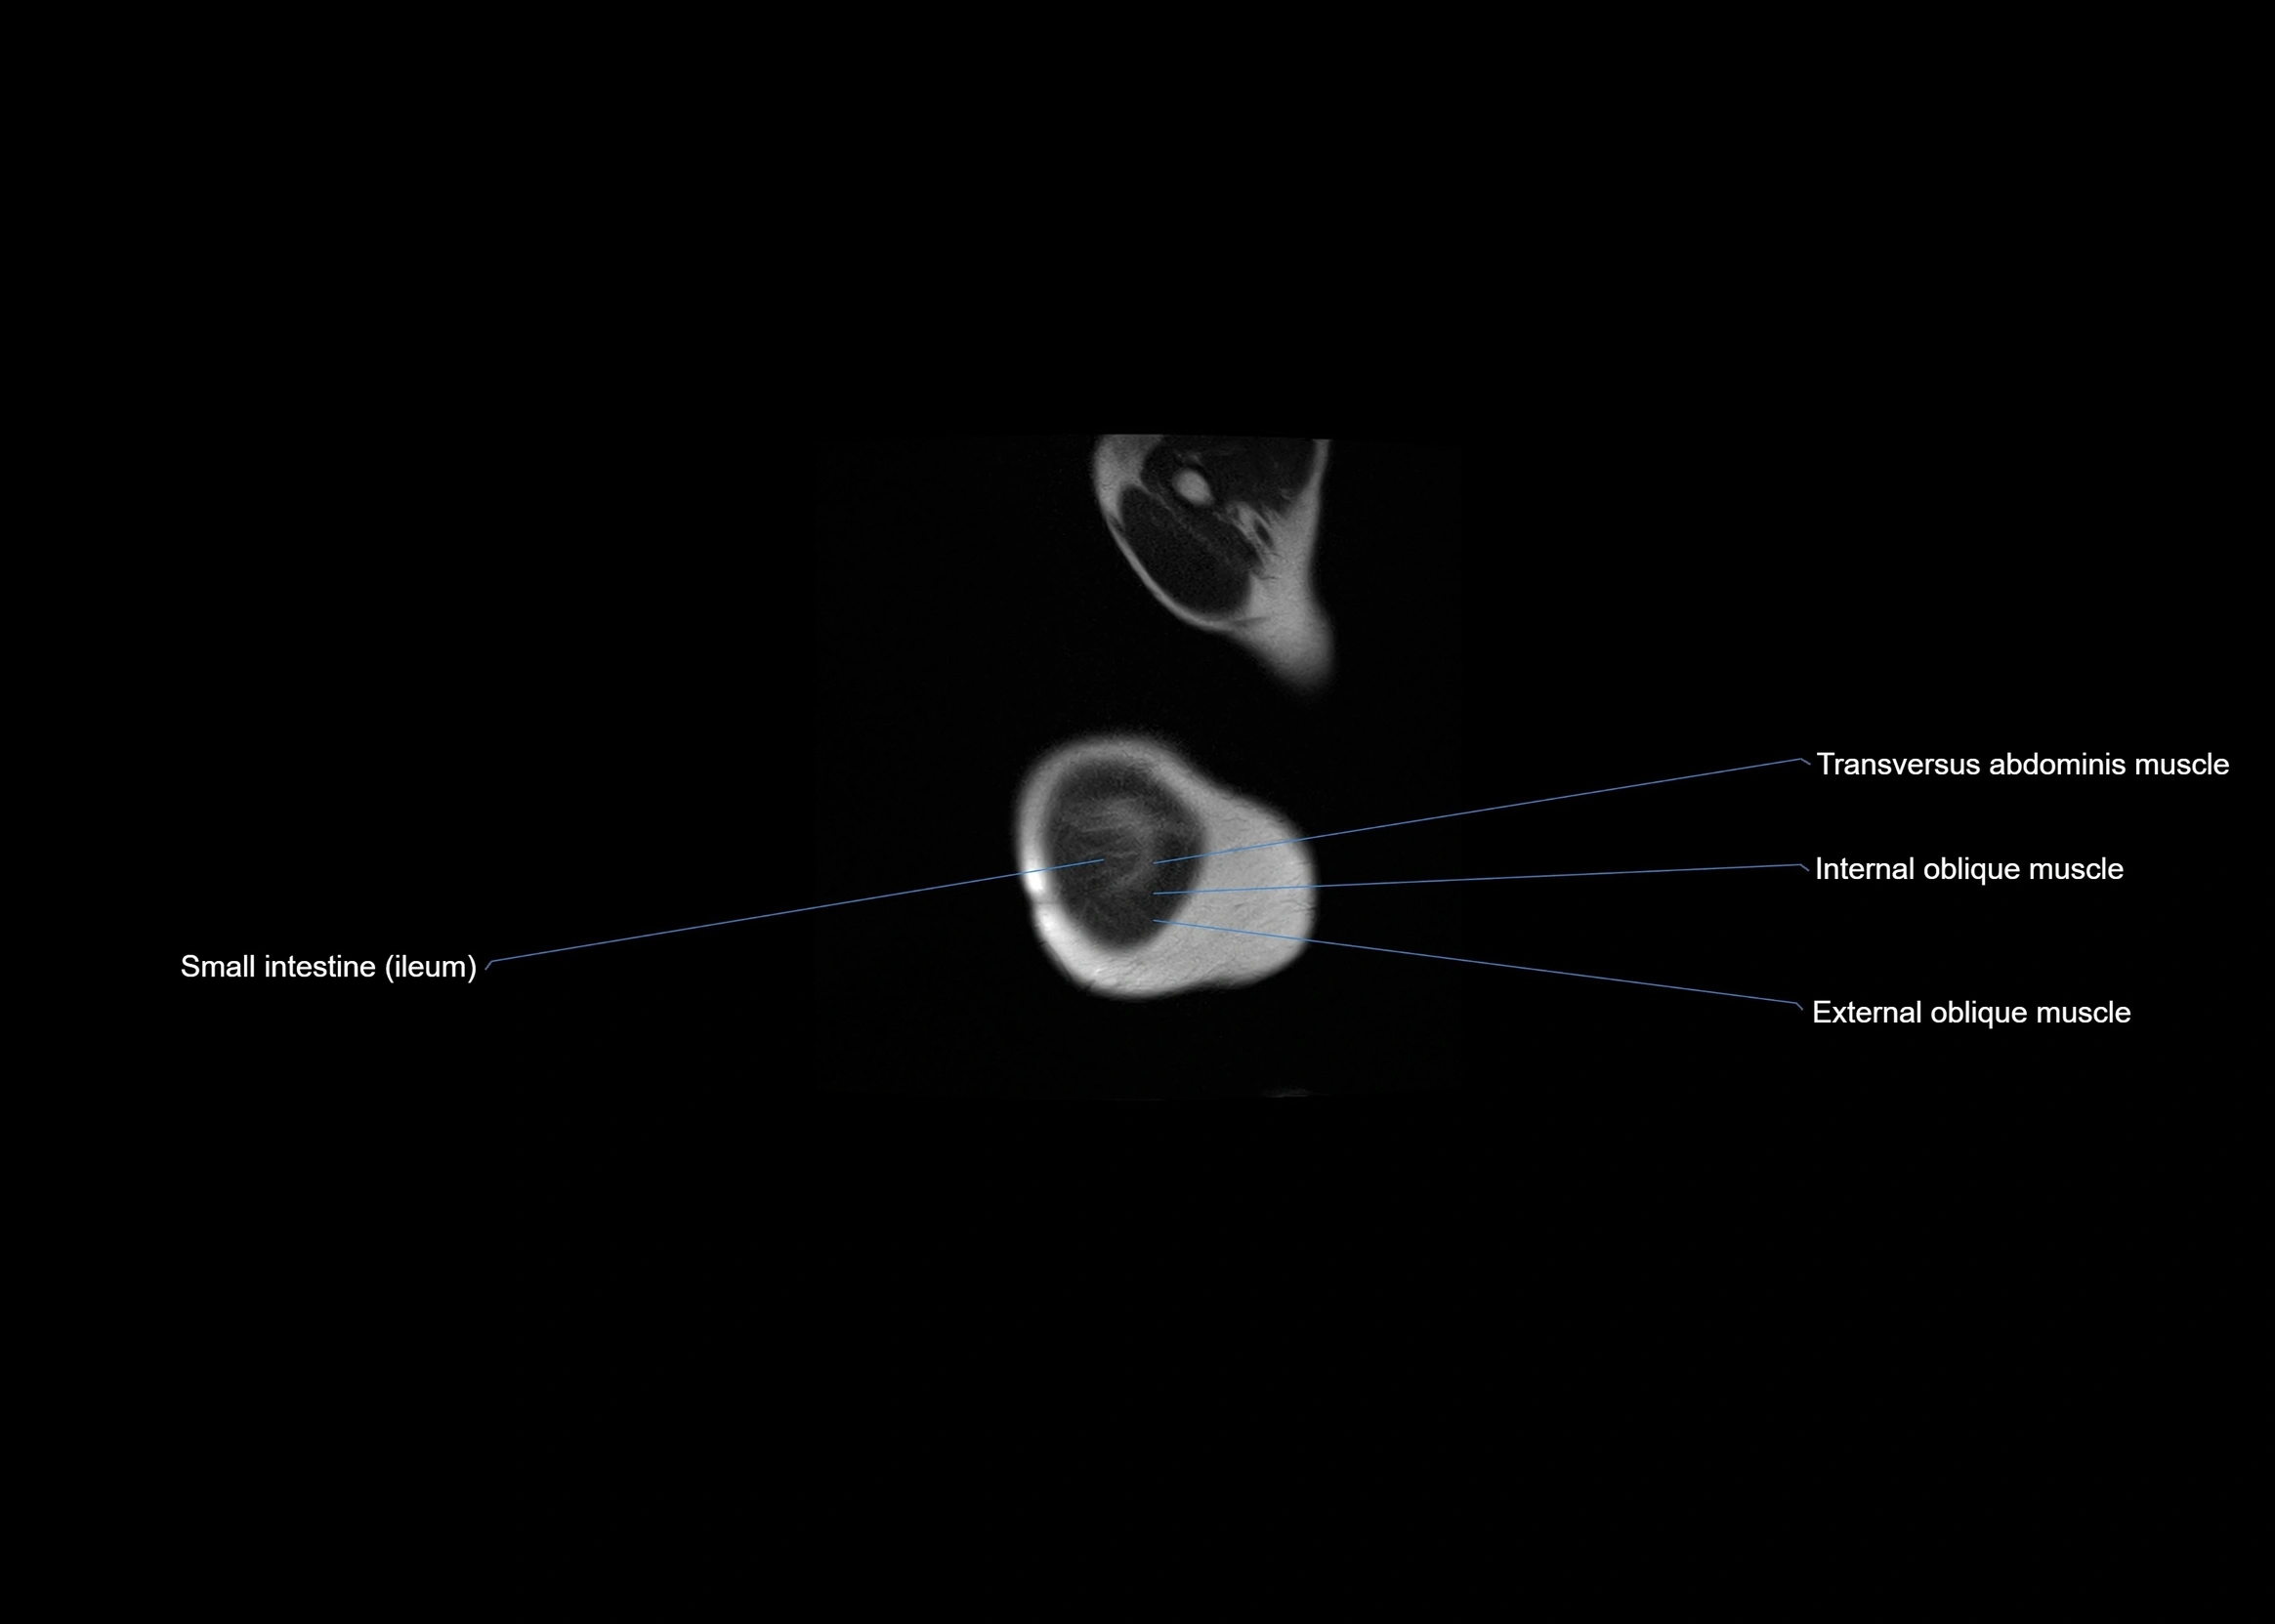

- External oblique muscle

- Internal oblique muscle

- Transversus abdominis muscle

- Small intestine